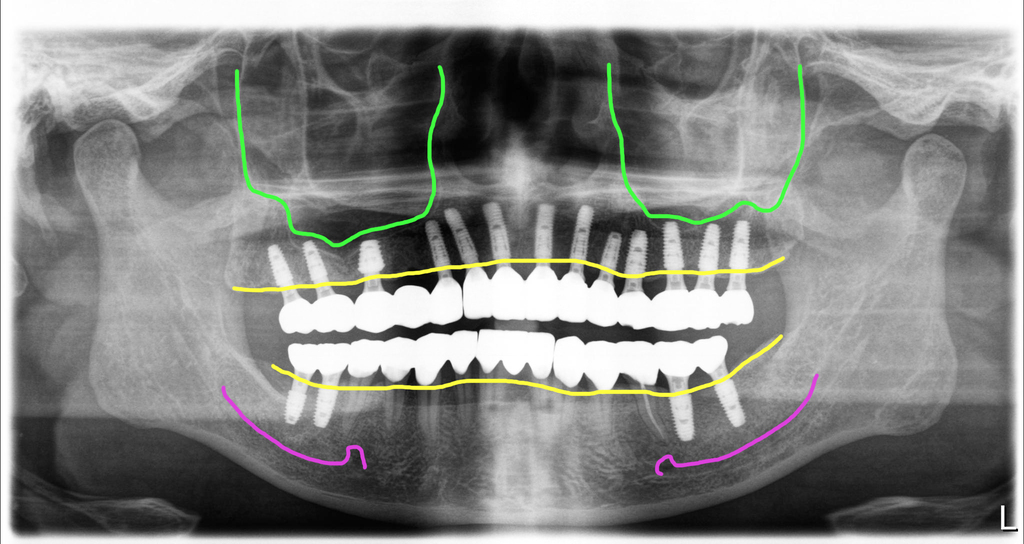

위13개, 아래4개 즉시 식립

위쪽에 염증이 너무 심한 치아 자리 한 군데만 제외하고 모든 부위에 해당하는 치아개수대로 임플란트를 식립했어요.

뼈상태는 양호하신 편이었고, 발치와 동시에 즉시 식립해서 초기고정도 좋았습니다. 위에는 10개의 임플란트에 지대주를 연결해서 수술당일 임시치아를 해 드렸고, 아래는 보철을 제거한 부위의 치아들을 임시치아로 하고 양쪽어금니부위에 심은 임플란트는 임시치아 적용을 하지 않았습니다.